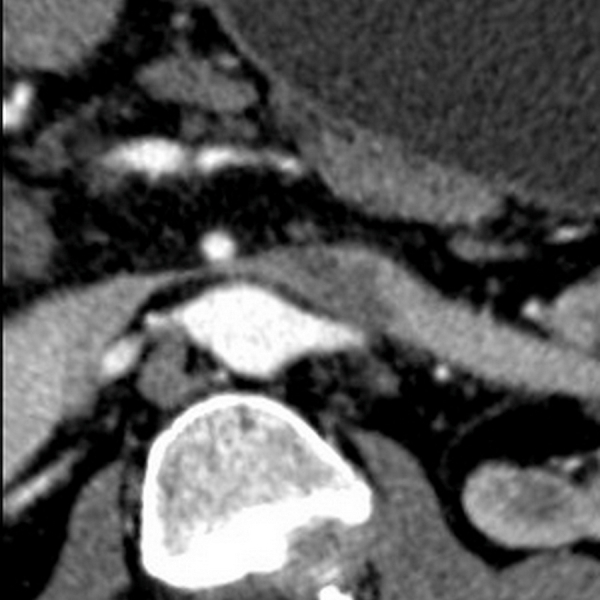

Left renal vein thrombosis with nutcracker syndrome.